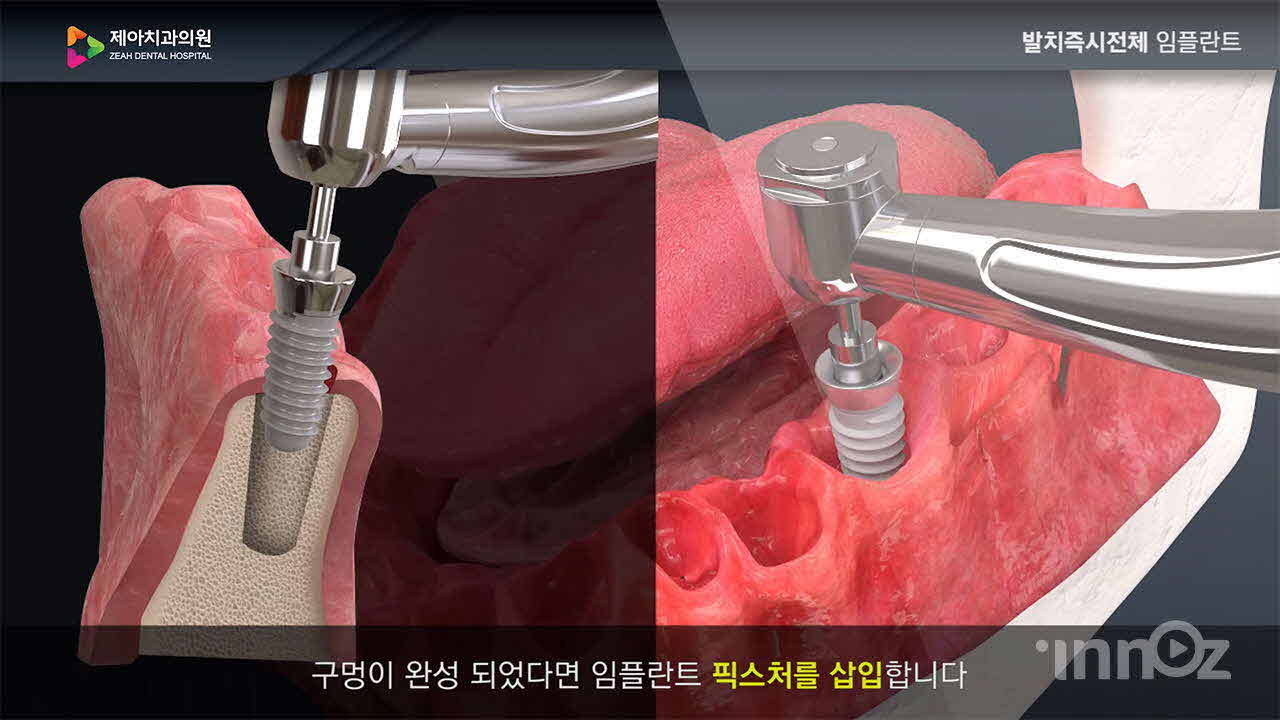

제아치과

파마리서치